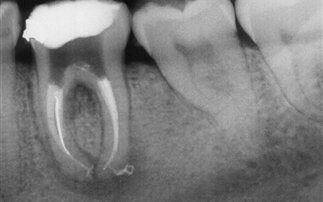

Επικίνδυνες οι συχνές ακτινογραφίες δοντιών

Αυξάνουν τον κίνδυνο εμφάνισης όγκων στον εγκέφαλοΤα άτομα που υποβάλλονται τακτικά σε ακτινογραφίες δοντιών διατρέχουν μεγαλύτερο κίνδυνο να εμφανίσουν όγκους του εγκεφάλου, επισημαίνει μελέτη αμερικανών ερευνητών που συνιστούν να αποφεύγονται τέτοιου είδους εξετάσεις σε ετήσια βάση.

Οι ασθενείς που υποβάλλονταν κάθε χρόνο σε ακτινογραφία δοντιών και εκτίθεντο συνεπώς σε ακτίνες Χ, διέτρεχαν από 1,4 φορές έως τριπλάσιο κίνδυνο να αναπτύξουν μηνιγγίωμα, σε σχέση με μια ομάδα μάρτυρα ασθενών σε καλή υγεία, επισημαίνει η μελέτη.

Το ποσοστό της συχνότητας των κρουσμάτων εξαρτάται από τον τύπο της οδοντικής εξέτασης που γίνεται, καθώς οι ακτίνες Χ μπορούν συνεπώς να χρησιμοποιούνται με διαφόρους τρόπους και από την ηλικία του ασθενή.